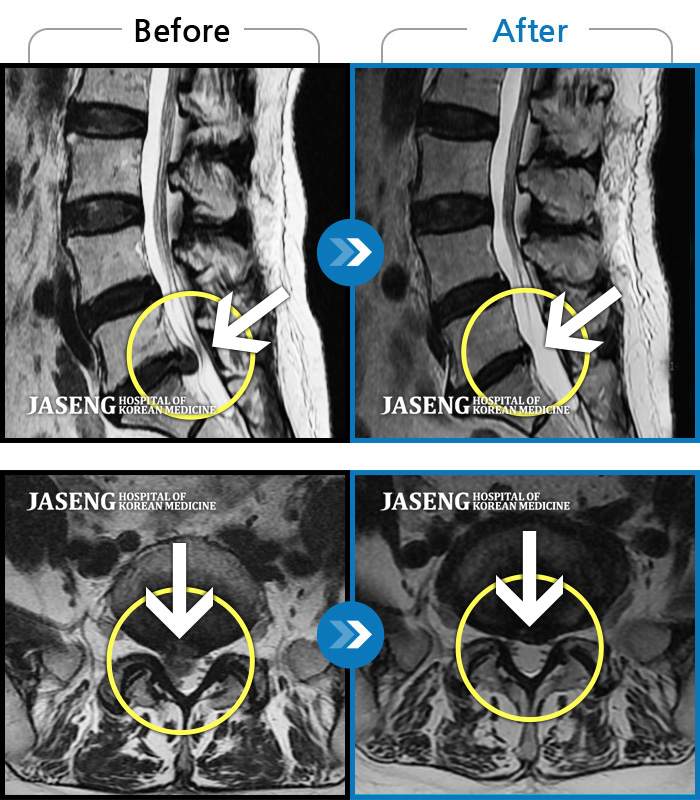

MRI ũ ʸ Ȯϼ.